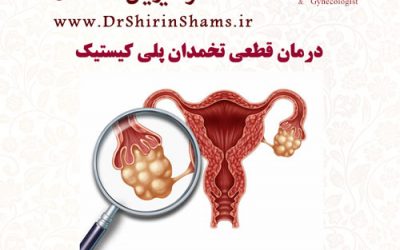

درمان قطعی تخمدان پلی کیستیک

سندروم تخمدان پلی کیستیک یا تنبلی تخمدان نوعی اختلال در غدد دورن ریز می باشد که بانوان را در سنین باروری درگیر می نماید. در این عارضه کیسه های کوچک حاوی مایعات بر روی تخمدان های فرد مبتلا رشد می نمایند و عوارضی را به دنبال می آورند. رشد بیش از حد...